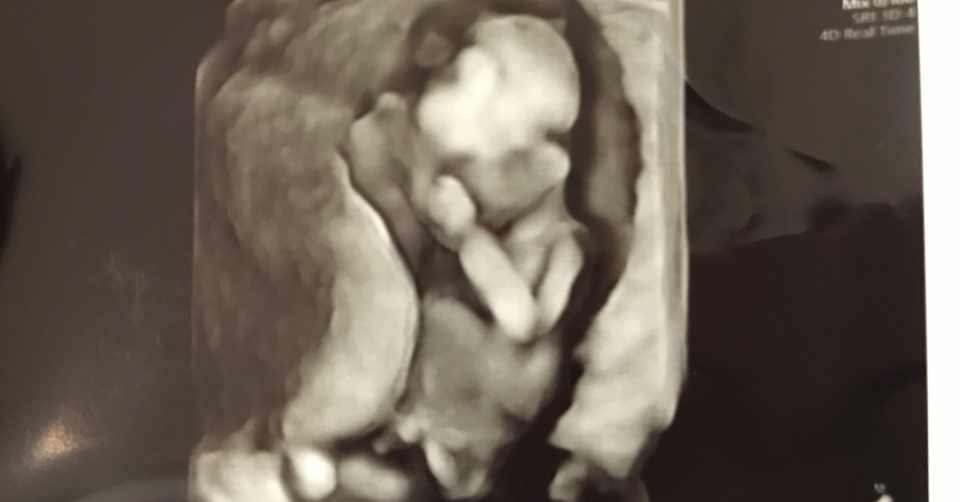

初めての4dエコー映像 妊娠18週の赤ちゃん 胎児 妊娠5ヶ月 18 Week

妊娠5ヶ月の胎児の4d映像です Youtube